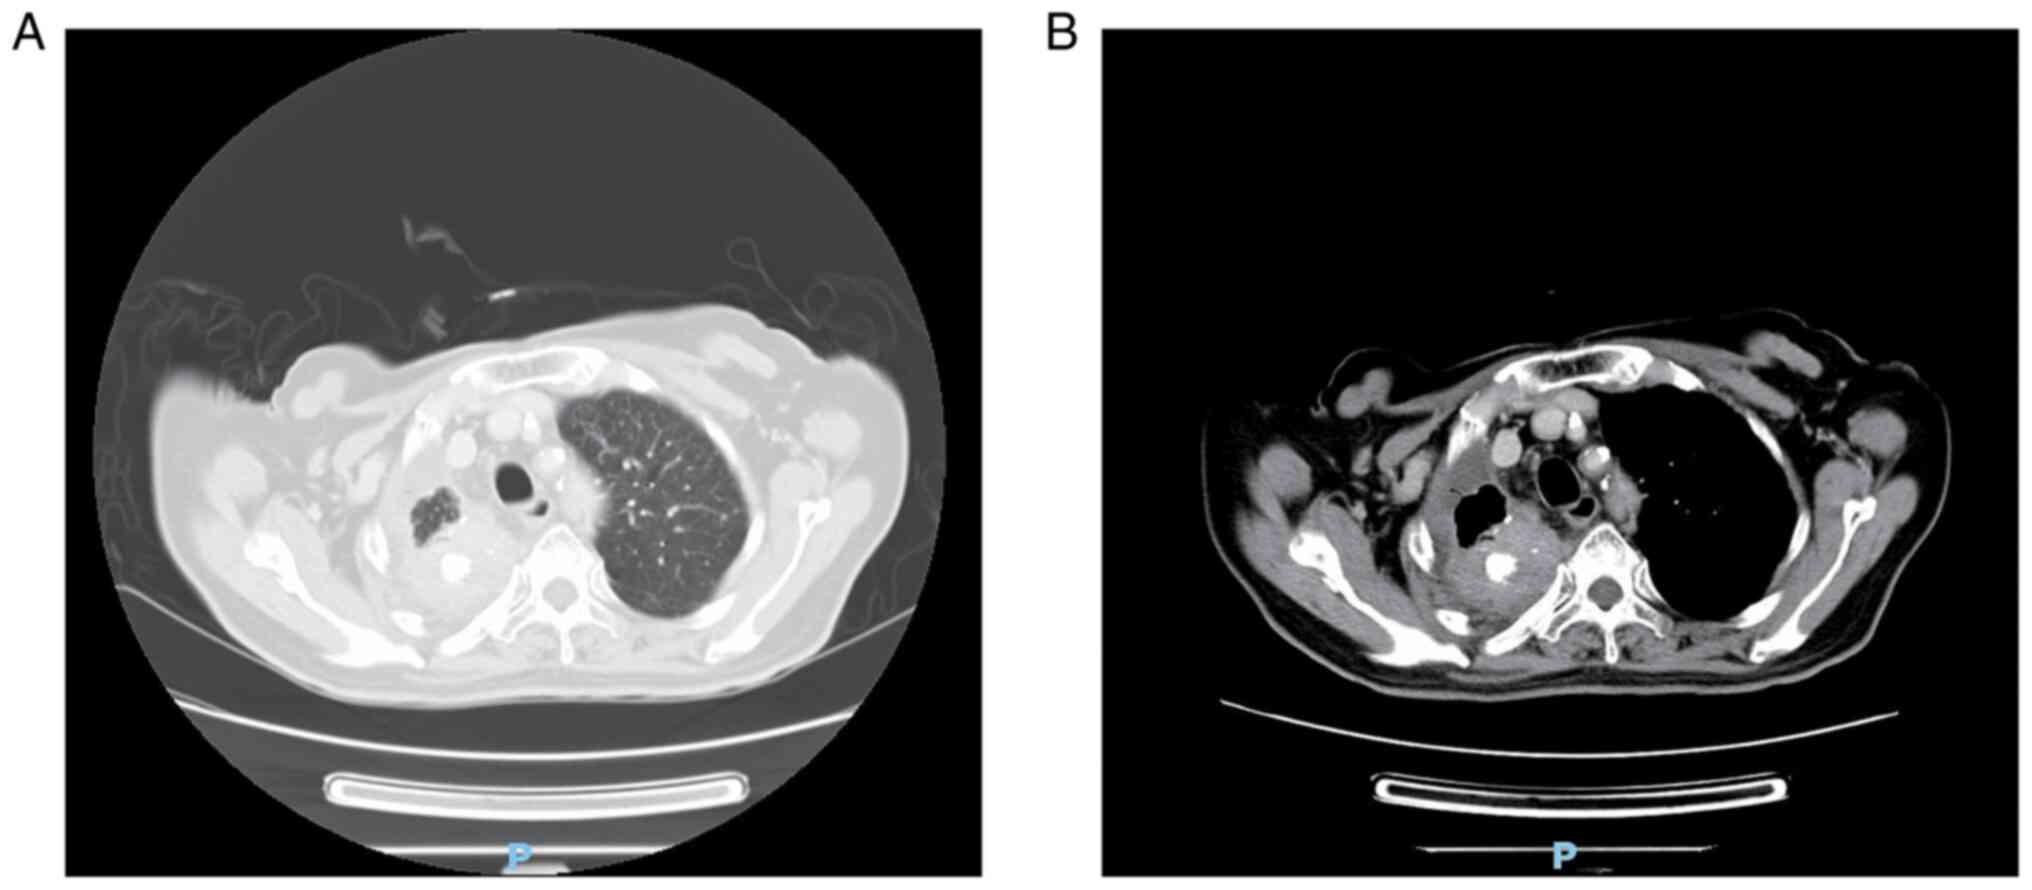

Endoscopic manifestations and treatment outcomes of asymptomatic gastric metastases from primary lung adenocarcinoma: Report of two cases

Metastatic spread of lung adenocarcinoma to the stomach is rare and most gastric metastases are discovered at the advanced stage due to certain symptoms. The present study reported two cases of asymptomatic gastric metastases from lung adenocarcinoma presenting as diminutive nodules or erosion endoscopically. The manifestations were also visualized under magnifying endoscopy with blue laser imaging (BLI‑ME), the two cases share certain common characteristics under BLI‑ME, such as an obviously widened intervening part and extended subepithelial capillary network, which indicated that lesions developed beneath the superficial epithelium. Target biopsy and further immunohistochemical staining confirmed that the gastric lesions were metastatic from primary lung cancer. None of the two patients were candidates for surgery due to multiple distant metastases, but the gastric metastases regressed to scars after systemic anticancer therapy. These two cases were presented in order to improve the current understanding of the endoscopic manifestations of early gastric metastases from lung cancer, and the outcomes may demonstrate that systemic treatment is effective for eliminating early gastric metastatic lesions.

Figure 1

Figure 2

Figure 3

Figure 4